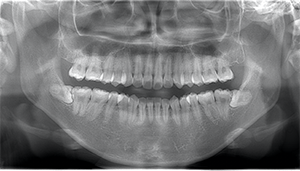

左下の歯茎が腫れている親知らずの症例

- 抜歯前写真(レントゲン、CT等)

左下の親知らず周囲歯肉が腫れていました。

また、手前の歯との間で虫歯もできていました。

| 抜歯内容 | 下顎の親知らずの抜歯希望の患者様です。 智歯周囲炎となっており、初診時では麻酔が効きづらい旨をお話しし、初診時は抗生物質をお出ししました。1週間後、ある程度歯肉の炎症がとれたことを確認して抜歯を行いました。 麻酔を行い、遠心(親知らずの奥側)歯肉と、手前の歯の頬側の歯肉を切開しました。 歯茎を開いて、手前の歯と引っかかっている部分をカットしました。 その後、骨からでている歯冠部(頭の部分)をカットしました。 その後へーベルで歯根(骨に埋まっている部分)を脱臼し、抜歯を終えました。 切開した歯茎を3針縫って、治療終了となりました。 歯茎を切ったため、3日ほど腫れぼったい感じがあったようですが、痛みはほとんどなく、治癒に向かいました。 |